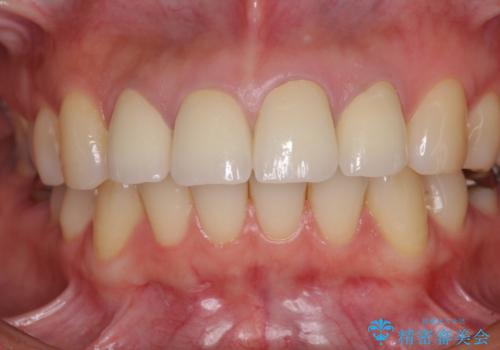

統一感があり、歯肉ラインもきれいに整い、清潔感溢れる口元に仕上げることができました。